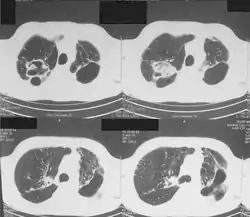

Infection

- Seems to be pathogenic in immunocompetent humans.

- Roth et al. 2000. Mycobacterium heckeshornense sp. nov., a new pathogenic slowly growing Mycobacterium sp. causing cavitary lung disease in an immunocompetent patient. J. Clin. Microbiol.,38, 4102–4107.